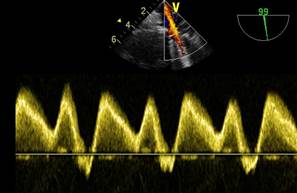

Se verifica con doppler color y espectral el adecuado flujo de la vena cava superior y de la vena pulmonar derecha en la zona próxima a la colocación del oclusor. (Figuras 11,12,13)